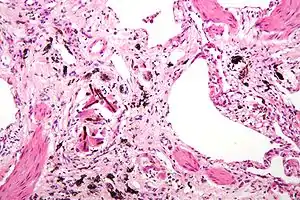

Asbestosis is the scarring of lung tissue (beginning around terminal bronchioles and alveolar ducts and extending into the alveolar walls) resulting from the inhalation of asbestos fibers. There are two types of fibers: amphibole (thin and straight) and serpentine (curly). All forms of asbestos fibers are responsible for human disease as they are able to penetrate deeply into the lungs. When such fibers reach the alveoli (air sacs) in the lung, where oxygen is transferred into the blood, the foreign bodies (asbestos fibers) cause the activation of the lungs' local immune system and provoke an inflammatory reaction dominated by lung macrophages that respond to chemotactic factors activated by the fibers.[19] This inflammatory reaction can be described as chronic rather than acute, with a slow ongoing progression of the immune system attempting to eliminate the foreign fibers. Macrophages phagocytose (ingest) the fibers and stimulate fibroblasts to deposit connective tissue. Due to the asbestos fibers' natural resistance to digestion, some macrophages are killed and others release inflammatory chemical signals, attracting further lung macrophages and fibrolastic cells that synthesize fibrous scar tissue, which eventually becomes diffuse and can progress in heavily exposed individuals. This tissue can be seen microscopically soon after exposure in animal models. Some asbestos fibers become layered by an iron-containing proteinaceous material (ferruginous body) in cases of heavy exposure where about 10% of the fibers become coated. Most inhaled asbestos fibers remain uncoated. About 20% of the inhaled fibers are transported by cytoskeletal components of the alveolar epithelium to the interstitial compartment of the lung where they interact with macrophages and mesenchymal cells. The cytokines, transforming growth factor beta and tumor necrosis factor alpha, appear to play major roles in the development of scarring inasmuch as the process can be blocked in animal models by preventing the expression of the growth factors.[20][21] The result is fibrosis in the interstitial space, thus asbestosis. This fibrotic scarring causes alveolar walls to thicken, which reduces elasticity and gas diffusion, reducing oxygen transfer to the blood as well as the removal of carbon dioxide. This can result in shortness of breath, a common symptom exhibited by individuals with asbestosis.[22]

Extensive fibrosis of pleura and lung parenchyma.